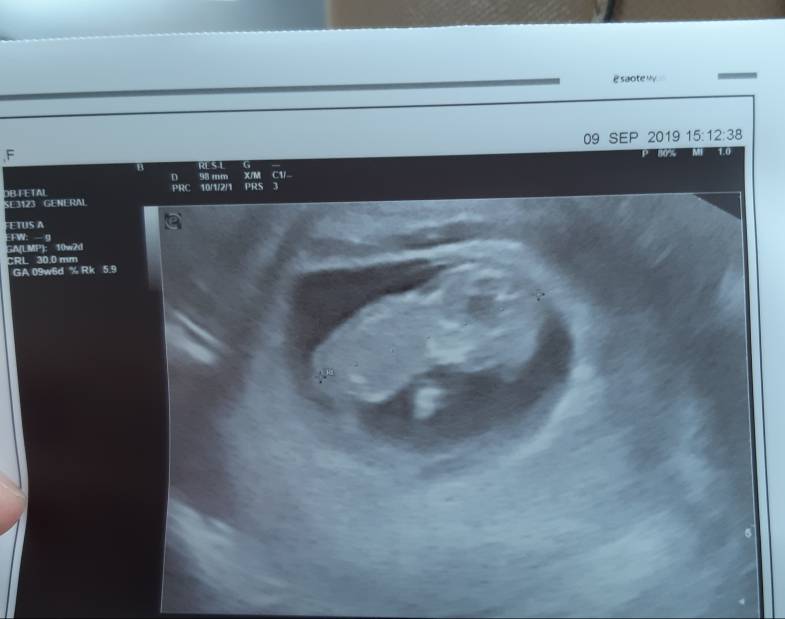

Moje maleństwo coraz większe [emoji173] już 3cm. Ale machało rączkami [emoji173] Ogólnie wszystko ok, ale mam krwiaczka i polipa, przez co mogę plamić i dopóki nie pojawi się żywo czerwona krew, mam się plamieniami kompletnie nie przejmować. Ogólnie Pan doktor powiedział, że jest wszystko dobrze, ale odetchnąć będzie można około 16-17 tygodnia (przez szczelinę przy krwiaczku). Także mam się oszczędzać i spokojnie czekać na kolejną wizytę :)Zobacz załącznik 1020314